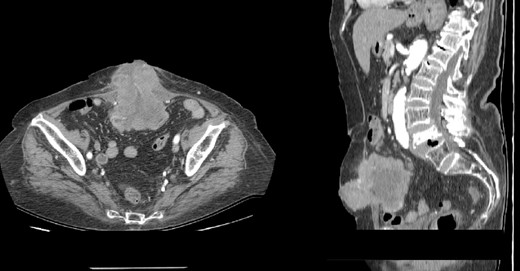

A contrast-enhanced abdominal computerized tomography (CT) revealed the existence of a soft-tissue irregularly contoured tumor originating from the small intestine that breaks through the anterior abdominal wall and penetrates and infiltrates the subcutaneous fat as well as the skin. The tumor was measured to have dimensions of 89 × 75 mm (Fig. 2). The patient was offered a surgical exploration. A midline laparotomy beginning above the umbilicus was performed and when extending it to the caudal, en-block resection of the anterior abdominal wall was performed along with the affected small intestinal loop (the mid-portion of the ileum) containing the tumor (Figs 3–5). Primary end-to-end anastomosis was created. The abdominal wall defect was closed with a primary suture with a relative tension present on the suture line. The postoperative hospital period was uneventful. The patient was discharged on postoperative day 9. After discharge, a superficial surgical site wound infection occurred and was treated in the outpatient ward.

(A–B) Contrast-enhanced abdominal CT scan showing intraabdominal tumor that infiltrates the abdominal wall and the surrounding skin (A-axial scan, B-sagittal scan).